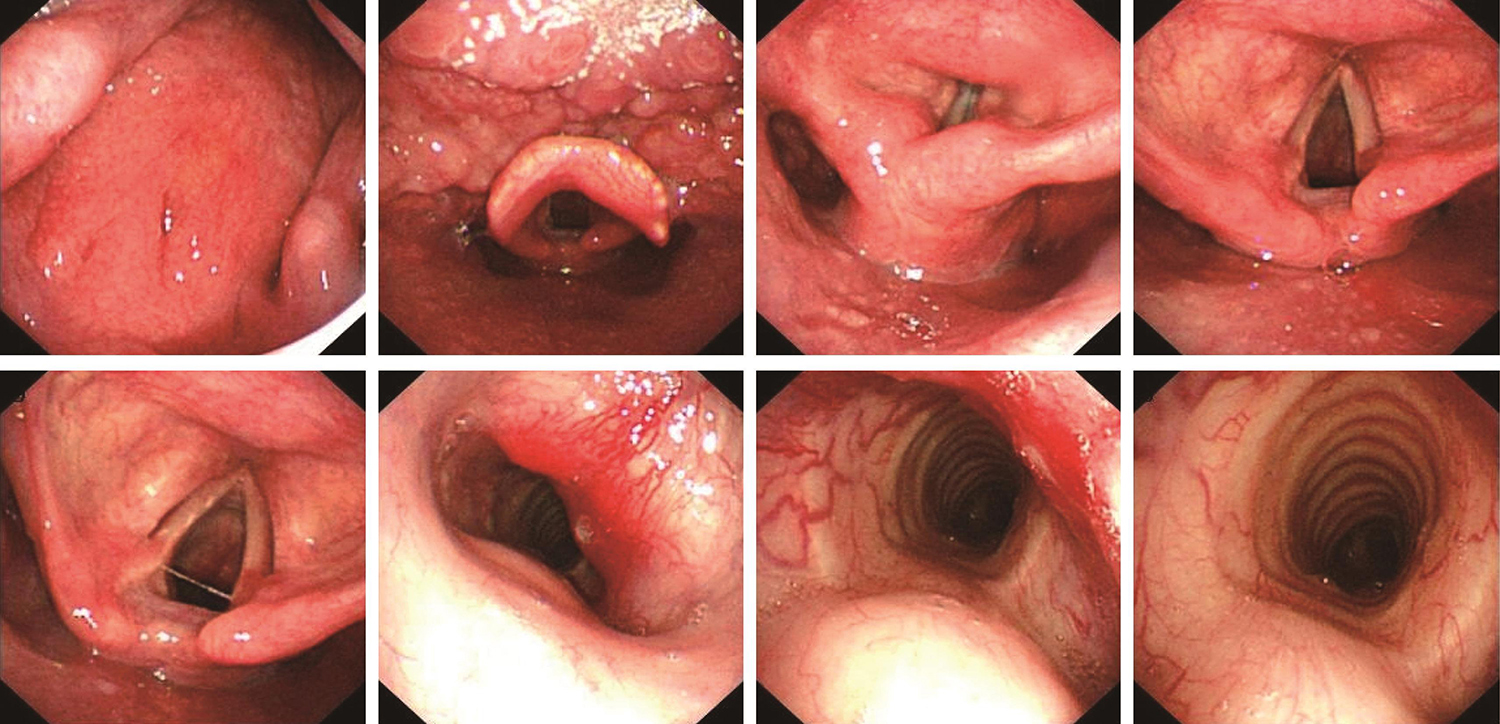

鼻腔进镜顺利。鼻咽部结构完整,黏膜光滑,未见明显异常。口咽双侧扁桃体未见肿大。舌根部淋巴滤泡增生。下咽部表面基本光滑,未见明显异常。双侧声带活动,未见明显受限。声门下、上段气管(距声带下约2.5cm)右前壁可见隆起性肿物,病变长度约2.0cm,气管腔略变窄(图4)。病变下方气管正常。

气管肿物,结合影像学检查,考虑为甲状腺癌侵及。

图4 内镜示气管肿物